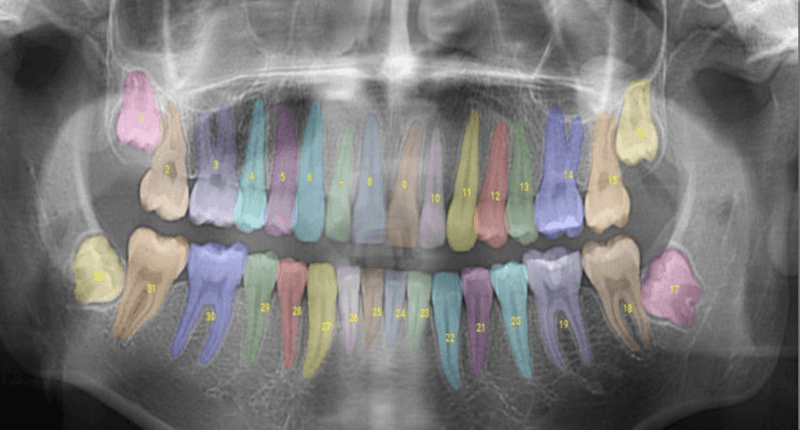

2018年に設立されたOverjetは、レントゲン写真の疾病診断、口腔の健康についての患者教育、歯科保険請求の審査などの基準をすでに引き上げています。同社のプラットフォームは、ミリメートルレベルの精度で口腔疾患の例を検出し、輪郭を描き、定量化する、米国食品医薬品局(FDA)から認可された唯一の技術です。

そして今、歯科医、保険会社、患者のすべてが、Overjetという同じ真実の情報源を手に入れました。Overjetは、何百万もの症例に対して高度な人工知能を訓練し、トップクラスの臨床専門家チームによってその精度を継続的に検証しています。FDAが実施した複数の調査では、Overjetを使用した場合、ほぼすべての一般歯科医で虫歯や歯石の検出精度が向上していました。

Overjetは、臨床医、歯科経営幹部、管理者、保険会社にとって不可欠なツールとなっています。訓練を受けた専門家はOverjetを使用して、診断、治療の推奨、請求の確認、効率的な業務運営を行っています。OverjetのAIは人間の判断を補強するものであり、人間の判断に取って代わるものではありません。すべての治療と給付の決定は、引き続き認定された専門家によって行われます。